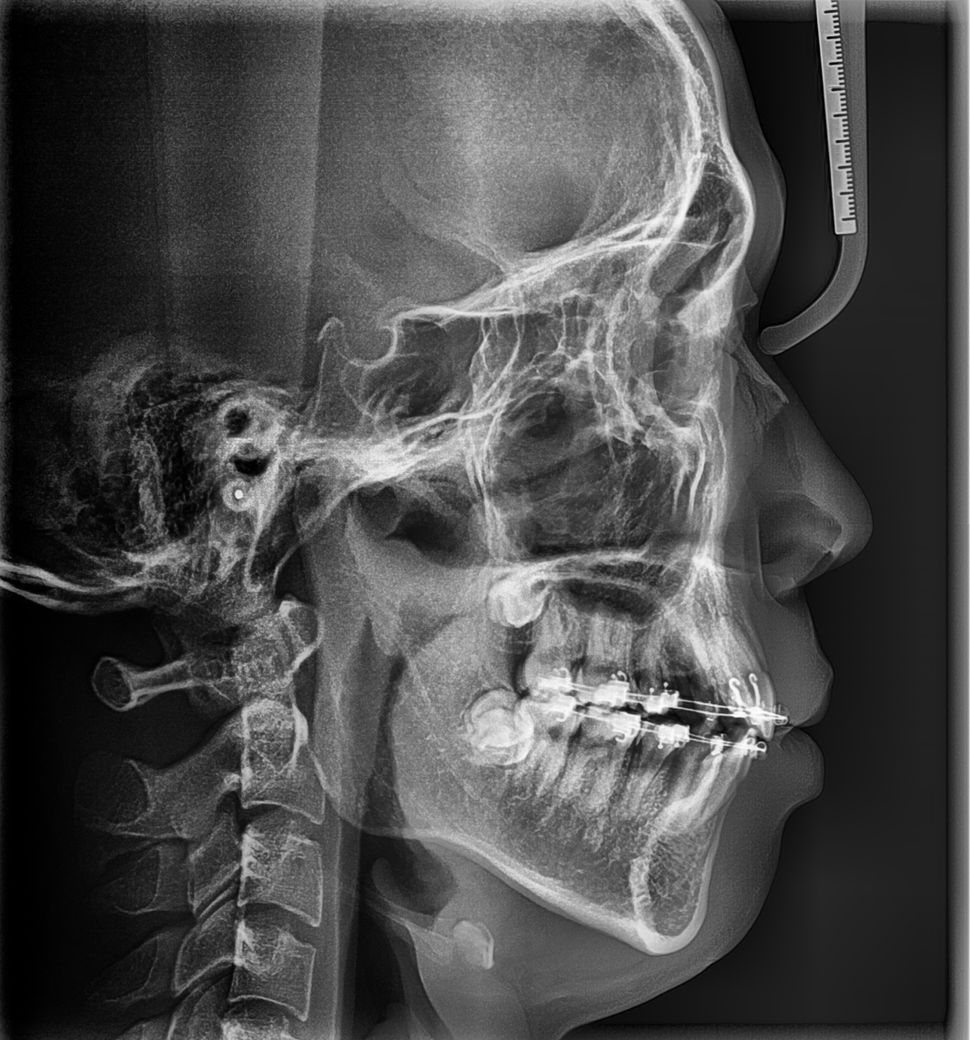

교정 중 1년 8개월차 됬을때 사진 입니다

• 2번 째 사진